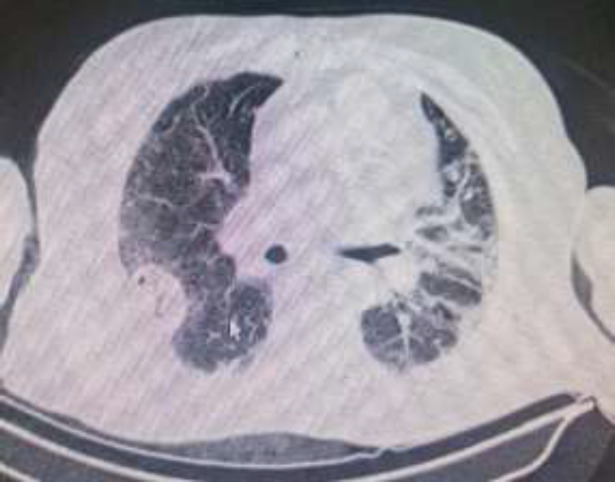

背景:我们的研究探讨了 COVID-19 后患者肺空洞的可能病因和特征。肺空洞是该病的晚期并发症,但它却导致多人转诊至我们位于伊朗德黑兰的三级医院:我们对 2020 年 4 月至 2021 年 9 月期间入住本中心的 20 名患者进行了回顾性病例系列研究。他们均被诊断为 COVID-19,并同时出现肺空洞。我们评估了他们在2021年的电子病历,并根据现有文献将他们的特征与其他研究进行了比较:结果:在 20 名龋齿患者中,12 人(60%)曾被诊断患有 COVID-19,9 人(45%)患有 2 型糖尿病。9名患者(45%)患有细菌性超级感染,4名患者(44%)患有真菌感染。所有患者都接受了皮质类固醇治疗,但只有4名患者(20%)额外使用了托珠单抗:结论:COVID-19 患者在康复期间可能会出现肺空洞,但这种不常见的放射学发现取决于特定的风险因素。

Background: Our study discusses the probable etiologies and characteristics of pulmonary cavities in post-COVID-19 patients. A pulmonary cavity is a late complication of the disease, yet it has led to multiple referrals to our tertiary hospital in Tehran, Iran.

Methods: We conducted a retrospective case-series study on 20 patients who were admitted to our center between April 2020 and September 2021. They were all diagnosed with COVID-19 and concomitantly developed pulmonary cavities. We assessed their electronic medical records in 2021 and compared their characteristics with other studies based on the available literature.

Result: Of the 20 patients with cavities, 12 (60%) had been diagnosed with prior COVID-19, and 9 (45%) had type 2 diabetes mellitus. 9 patients (45%) had bacterial superinfections while 4 (44%) had fungal infections. All patients received corticosteroids, but only 4 (20%) were additionally administered Tocilizumab.

Conclusion: COVID-19 patients can develop pulmonary cavities during recovery; however, this infrequent radiologic finding depends on specific risk factors.